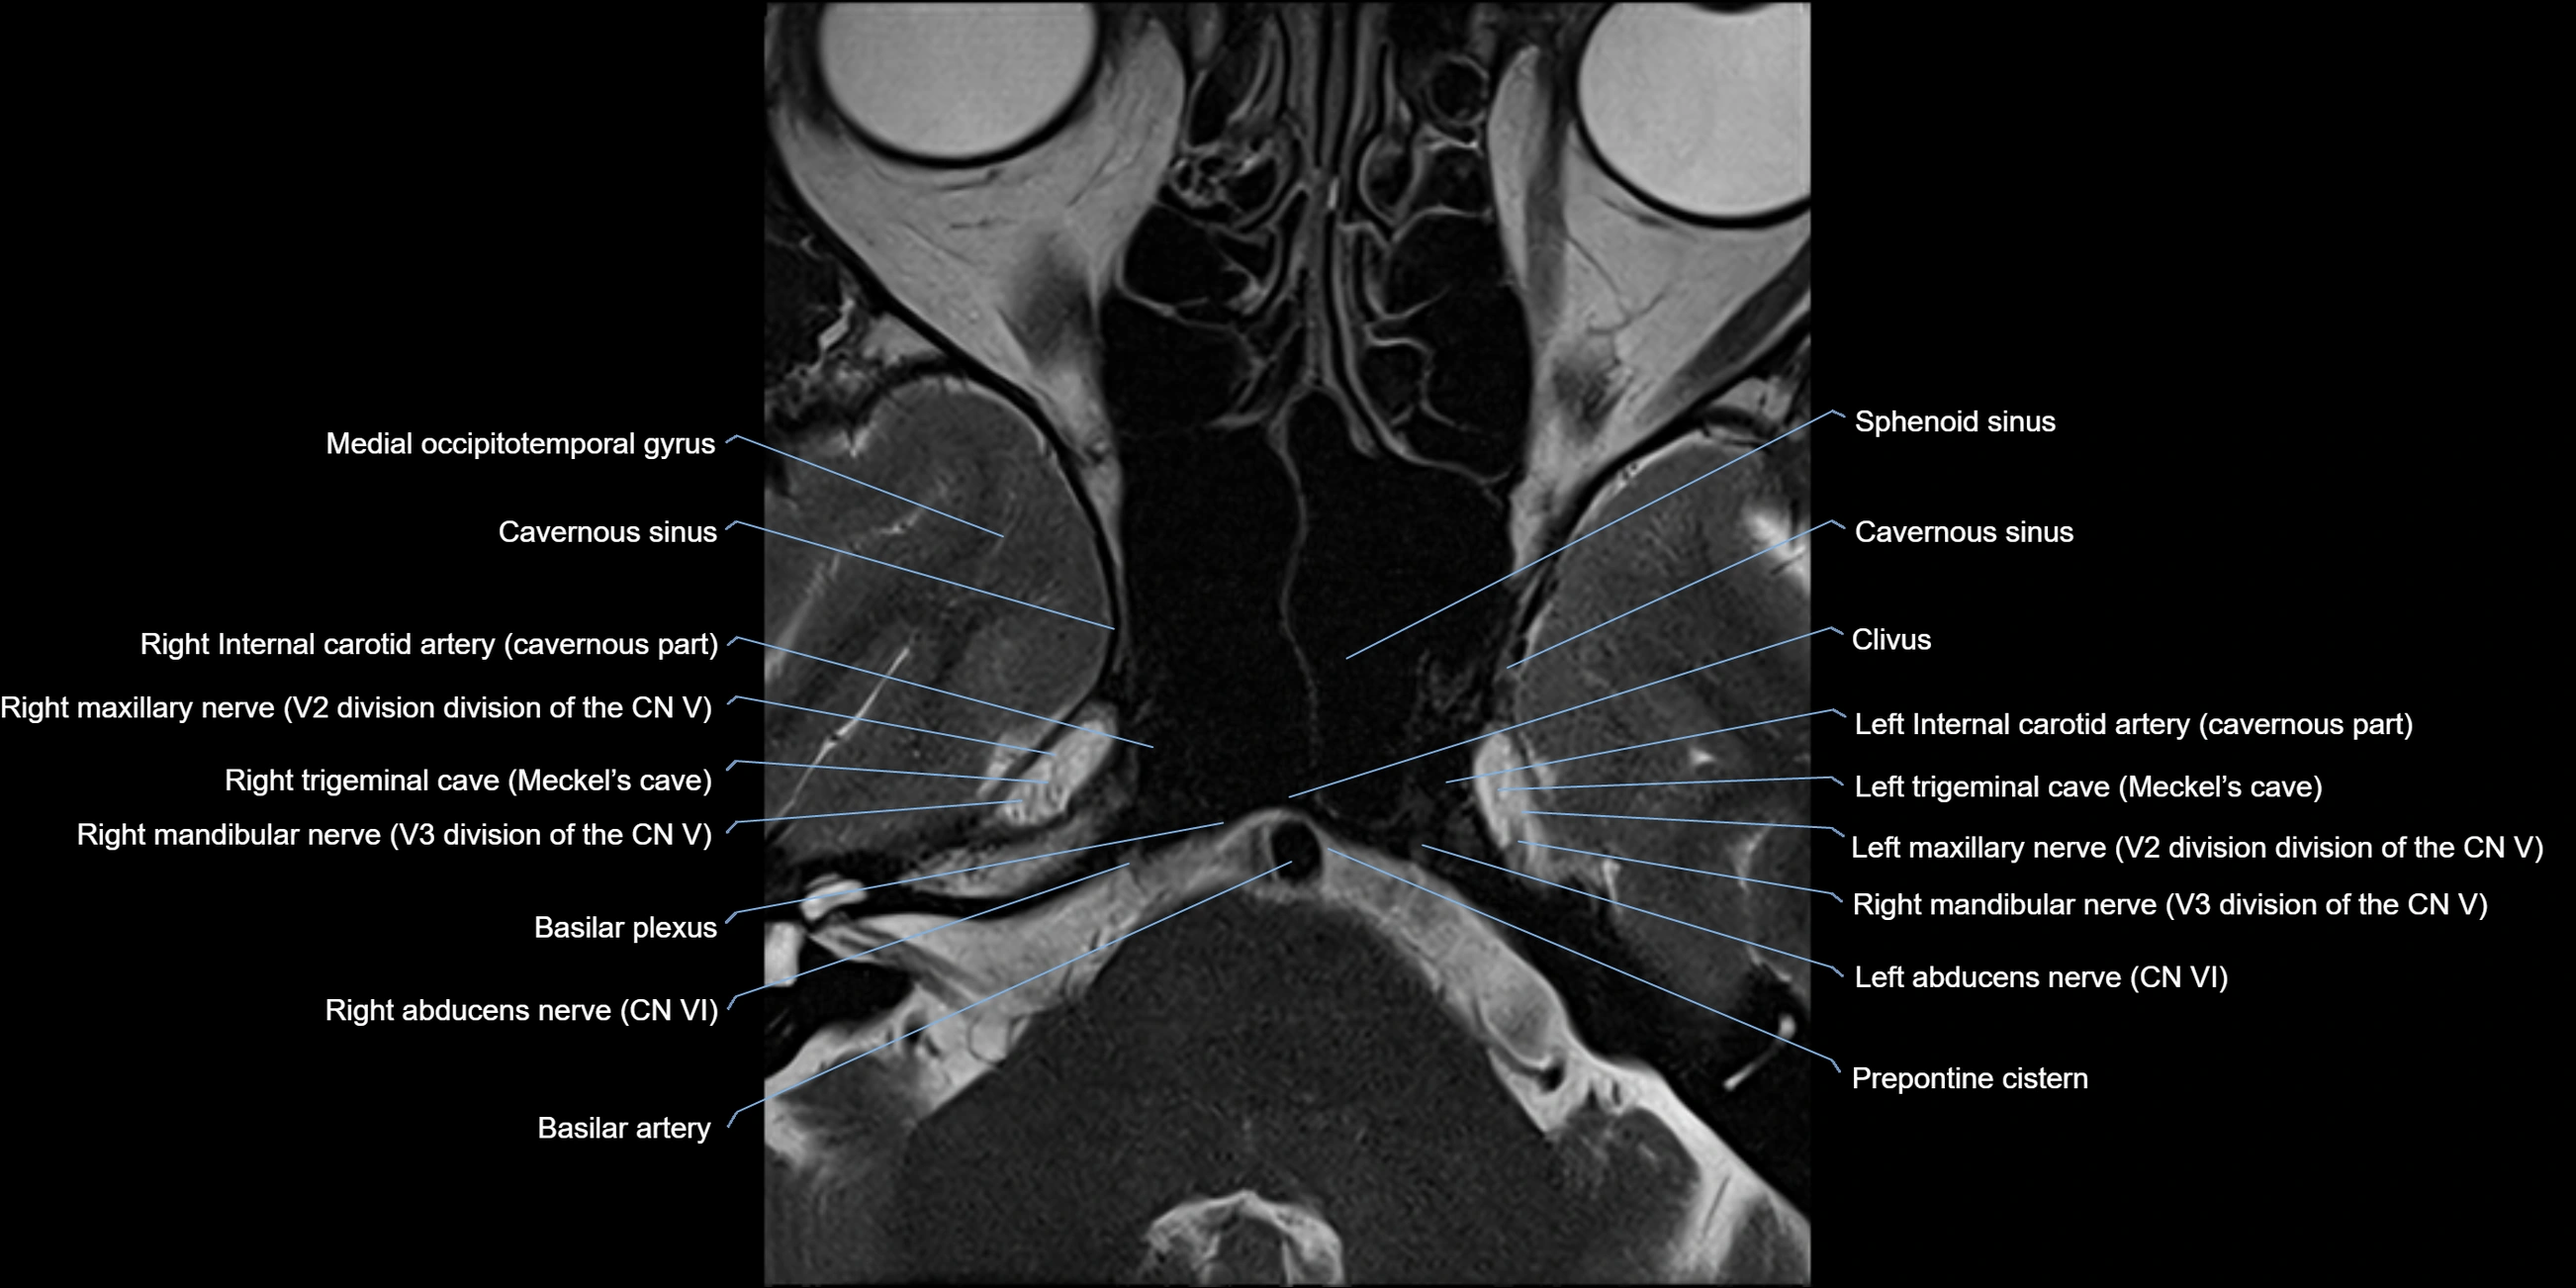

MRI Appearance

The abducens nerve is a small, thin, linear structure

Best visualized on high-resolution T2-weighted 3D MRI sequences (e.g., FIESTA or CISS)

Seen as a hypointense (dark) line running from the brainstem at the pontomedullary junction, traversing the prepontine cistern, and entering Dorello’s canal under the petrosphenoidal ligament, then into the cavernous sinus, and finally the orbit

May be challenging to visualize in standard MRI due to its small size

Pathology may be inferred by absence, displacement, or enhancement of the nerve

MRI images